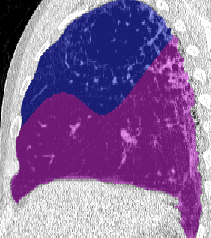

Lobar segmentation results for the proposed method and PTK are shown in Figure 5 for right lungs and Figure 6 for left lungs. For each image in the COVID-19 dataset (133 images in total), the lobar segmentation result was used to extract the amount of poor aeration () and consolidation () in each lobe. Common phenotypes of COVID-19 affected lungs were identified by hierarchical clustering over the fraction of poorly aerated and consolidated tissue in each lobe. Dendrographic analysis in Figure 7 reveals four primary clusters of patients that were identified by the hierarchical clustering: (a) mild loss of aeration primarily in the two lower lobes without consolidation; (b) moderate loss of aeration focused in the two lower lobes with or without consolidation in lower lobes; (c) severe loss of aeration throughout all lobes with or without consolidation; and (d) severe loss of aeration and consolidation throughout all lobes.

Our lung segmentation which identifies left and right lungs can be used as input to the LobeNet algorithm to achieve lobar segmentation. The lobar segmentations can be used to quantify involvement of disease at the lobar level, and thus may identify clusters of patients with similar phenotypes indicative of disease stage or prognosis. Pan et al. reported predominant lower lobe involvement in early disease that progresses to all lobes at the peak of disease severity [25]. Inui et al. reported similar findings in the Diamond Princess cohort and also found that 83% of asymptomatic patients have more ground glass opacities than consolidation compared to only 59% of symptomatic patients [26]. The four quantitatively identified clusters in our study match the results of qualitative scoring performed by radiologists in these studies [25, 26]. Cluster (a) is similar to early disease phenotype with predominantly ground glass opacities in the lower lobes; cluster (d) is similar to peak disease phenotype with large amounts of consolidation and ground glass opacities in all lobes; and clusters (b) and (c) may represent transitional phenotypes. Clinical information could be used to validate this analysis. Huang at el. performed a similar lobar analysis using a deep learning approach and also reported increasing opacification with disease progress. However, they did not show lobar segmentation results in a manner that allows us to qualitatively assess their accuracy [27].